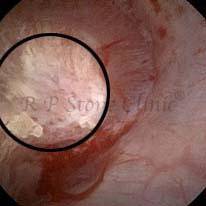

These images are taken as snap shots from the video recording of RIRS Surgery done at our hospital. These are Randall’s Plaques seen with Digital FLEX XC & Digital FLEX XC S. The cream or whitish patches are seen on the tips of RENAL PAPILLAE as seen in images below.

The Below Images Show Small Stones attached to the Renal Papillae.